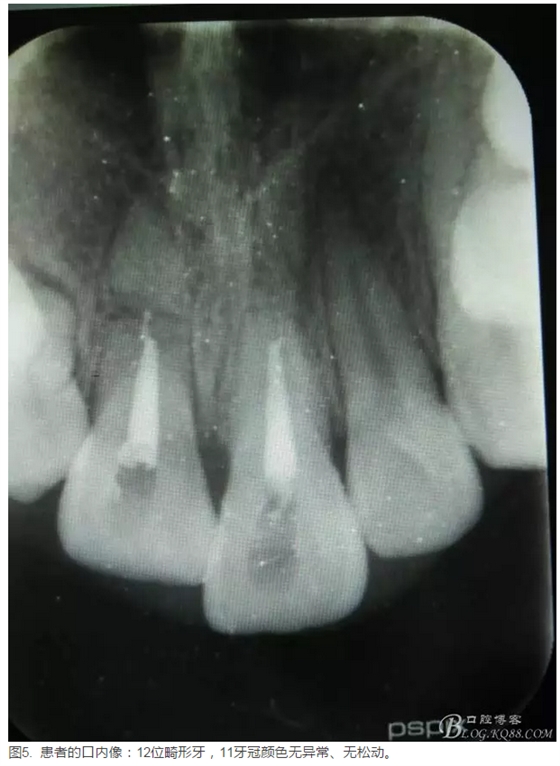

患者、李xx、男、15歲,主訴:牙不齊,矯正牙齒。??茩z查:發(fā)現(xiàn)11、21根尖三分之一折斷,患者否認有外傷史。正畸科治療建議如圖1.。術前簽手術同意書。